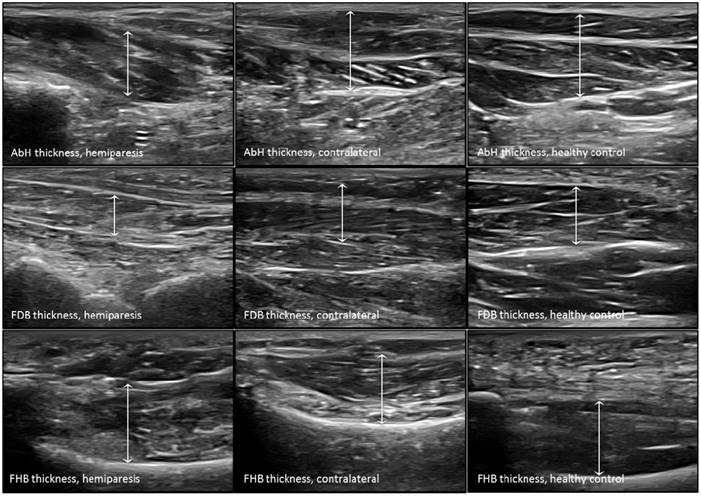

Figure 3

Ultrasound imaging measurements of the intrinsic plantar muscles thickness. Abbreviations: AbH, abductor hallucis; FDB, flexor digitorum brevis; FHB, flexor hallucis brevis.

The probe was located according to prior research studies about RUSI measures of the intrinsic plantar muscles and fascia [8-10]. First, the PF was assessed in a longitudinal line from the medial calcaneal tubercle to the 2nd toe. The PF was divided into 3 points of evaluation: 1) the calcaneus insertion (PF-1), b) the navicular tubercle (PF-2), and 3) the 2nd metatarsal head (PF-3). Second, the CSA (perpendicular to the muscle fibers) and the thickness (longitudinal to the muscle fibers) were assessed in the thickest part of the muscles (AbH, FDB and FHB) coinciding with 3 different scanning lines. Indeed, the AbH scanning line was located from the medial calcaneus bone tuberosity to the navicular bone tuberosity. After, the FDB scanning line was placed between the medial calcaneus tuberosity bone tubercle to the 3rd toe. Lastly, the FHB scanning line was longitudinally placed along the 1st metatarsal shaft (8,9). Regarding the RUSI measurements of the PF thickness (Figure 1), intrinsic plantar muscles CSA (Figure 2) and thickness (Figure 3) obtained in the hemiparesis, contralateral and healthy matched control feet, subjects who presented difficulties to evaluate the muscles and PF limits (i.e. structures larger than the probe footprint or ultrasound images with poor visually perimeters) were excluded [10].

The RUSI measurements regarding the CSA and thickness of the intrinsic plantar muscles and fascia between all groups were summarized in Table 2. Considering the intrinsic plantar muscles, statistically significant differences (P < 0.001) were only shown for the FHB thickness. The post-hoc Bonferroni´s analysis showed statistically significant differences for a FHB thickness increase of the hemiparesis feet (means difference of 0.31 cm; P < 0.001) and contralateral feet (means difference of 0.37 cm; P < 0.001) with respect to the healthy matched control feet. Regarding the fascia, statistically significant differences (P < 0.01) were only shown for the PF-2 and PF-3 thickness. The post-hoc paired Wilcoxon analysis showed statistically significant differences for a PF-2 thickness reduction of the hemiparesis feet (means difference of -0.03 cm; P = 0.006) and contralateral feet (means difference of -0.04 cm; P = 0.005) with respect to the healthy matched control feet. In addition, a PF-3 thickness reduction of the contralateral feet (means difference of -0.03 cm; P = 0.001) with respect to the healthy matched control feet. The rest of measurements did not show any statistically significant difference (P > 0.01).